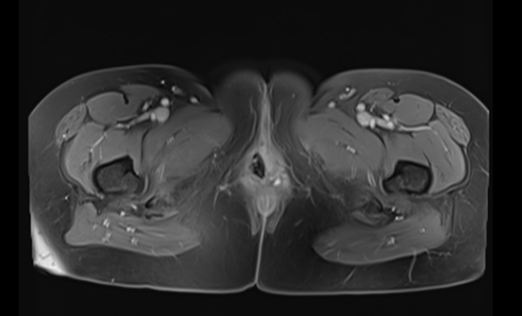

随后的近距离放疗(后装),以及两周期的“替雷利珠单抗注射液+TP”方案化疗,还有长达两年的“替雷利珠单抗注射液”维持治疗,在医护团队的精心照料下,赵女士的病情持续好转。期间复查影像学显示,肿瘤没有复发进展,曾经困扰她的外阴瘙痒、肿胀、疼痛也明显好转。